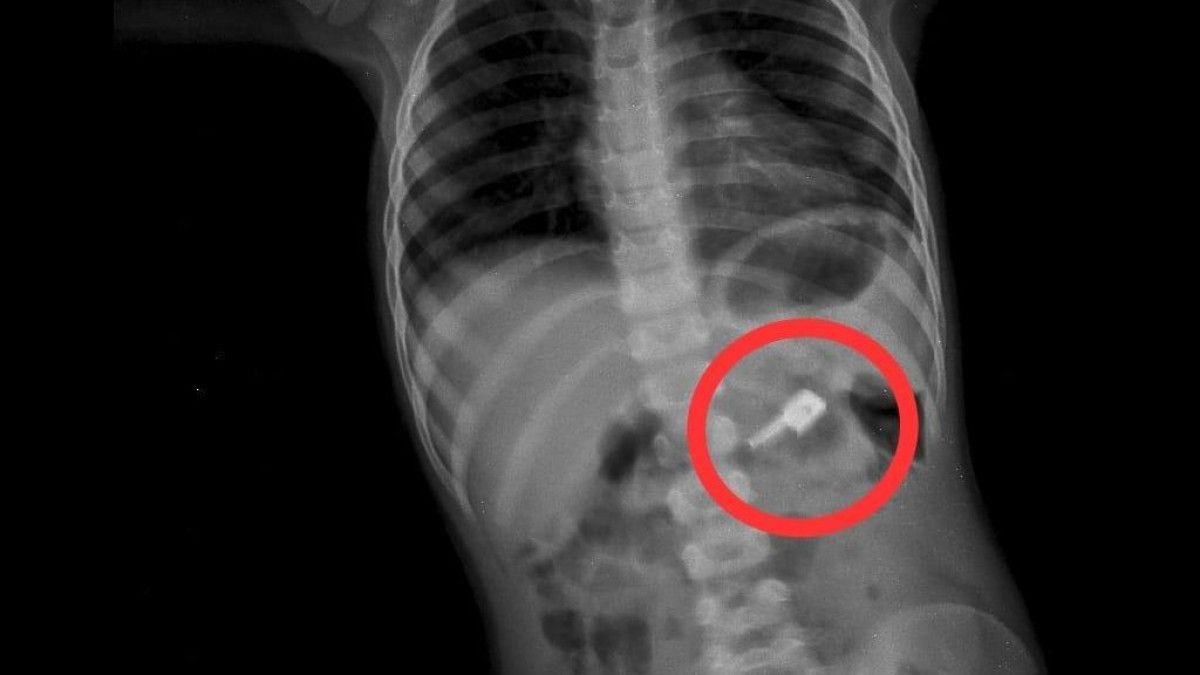

За маленького пациента взялись заместители главврача Сейдахмет Чинибеков и Маулим Кенжалы. На рентгенограмме брюшной полости они заметили в желудке мальчика не только бегунок, но и иголки.

"При проведении процедуры ЭФГДС из желудка удалили одну иглу, бегунок отсутствовал. Пациента оставили в хирургическом отделении под наблюдением специалистов. В результате бегунок со стулом вышел самостоятельно. Однако другая игла осталась. На контрольной R–грамме обнаружили еще две иглы в верхнем этапе брюшной полости и одну иглу в проекции таза. Проведена повторная ЭФГДС и удалена игла из желудка. Затем при помощи колоноскопии удалена игла, фиксированная в сигмовидной кишке", - сообщил врач-хирург высшей категории Сейдахмет Чинибеков.

Ребенок продолжал находиться под наблюдением. Еще одна рентгенограмма показала, что четвёртая игла находится в области таза.